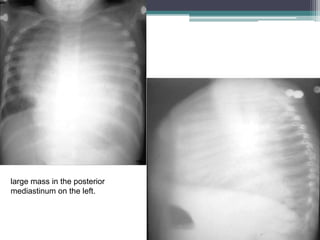

large mass in the posterior

mediastinum on the left.

Bone window images from a chest CT exam from the day of diagnosis demonstrate a

large spherical calcified left paravertebral mass measuring 12 x 11 x 8 cm in size. There

is a pleural effusion and a shift of mediastinal structures to the right. The mass appears

to extend via the retrocrural space into the abdomen causing displacement of the left

kidney and inferior vena cava. The mass crosses the midline. Some minimal thoracic

vertebral body remodeling and rib thinning is seen on the left. No spinal canal invasion

or liver metastases are seen